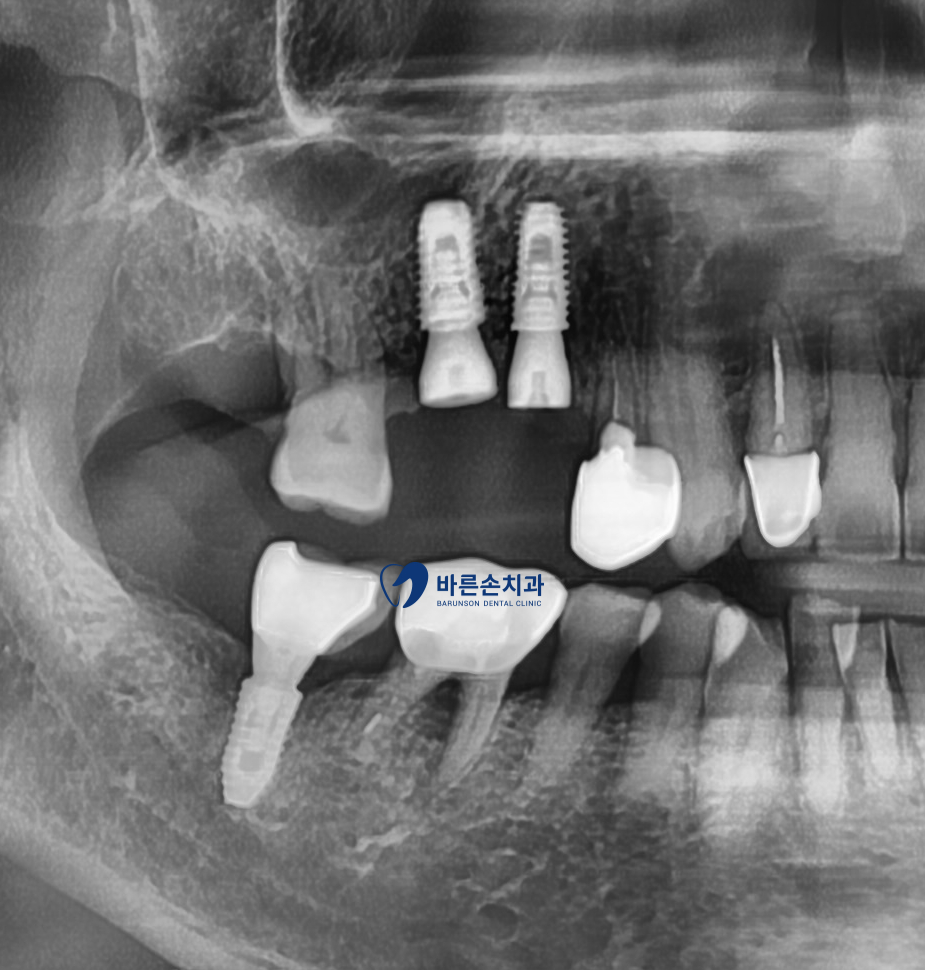

염증으로 인해 치조골 손상도가 높은 케이스라 상악동 거상과 치조골 이식을 동반하였습니다

이로 인해 알맞은 위치에 임플란트가 잘 고정되어져있는게 보이네요^^

이로 인해 충분한 치조골 이식과 임플란트의 공간을 확보하게 되며

보다 안정적인 임플란트 사용을 기대할 수 있습니다

드디어 완성 되었네요^^